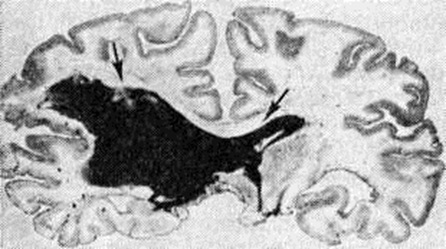

Геморрагический инсульт, как правило, возникает при заболеваниях, протекающих с повышенным артериальное давление. Это обусловлено тем, что сосудистые кризы (смотри полный свод знаний), характерные для гипертонической болезни (смотри полный свод знаний) и артериальной гипертензии (смотри полный свод знаний Гипертензия артериальная), приводят к морфологический изменениям стенок внутримозговых сосудов с нарушением их проницаемости — плазматическому пропитыванию (рисунок 1), некрозам (рисунок 2), образованию микроаневризм (рисунок 3) и их разрывам. Разрыв врождённых артериальных и артериовенозных аневризм может протекать на фоне нормального давления. Преимущественная локализация и характер геморрагий определяются особенностями ангиоархитектоники различных отделов мозга. При гипертонической болезни наиболее тяжёлым изменениям подвергаются сосуды подкорковых узлов и зрительного бугра. Это объясняется отхождением глубоких ветвей под прямым углом от средней мозговой артерии, являющейся продолжением внутренней сонной артерии, и незначительным числом анастомозов сосудов в этой области. В связи с этим на вскрытии кровоизлияния наиболее часто (40%) обнаруживаются в подкорковых узлах с распространением в прилежащее белое вещество (так называемый латеральные кровоизлияния, то есть расположенные латерально от внутренней капсулы, рисунок 4). Второе место по частоте (16%) занимают обширные кровоизлияния, разрушающие подкорковые узлы, внутреннюю капсулу, зрительный бугор (так называемый смешанные кровоизлияния — рисунок 5). Кровоизлияния в зрительный бугор (так называемый медиальные — рисунок 6) составляют 10%, в мозжечок — 6—10%, в мост мозга — 5% от общего числа внутримозговых геморрагий. Кровоизлияния только в белое вещество полушарий мозга встречаются крайне редко. Подразделение полушарных кровоизлияний на латеральные, медиальные и смешанные имеет особое значение в связи с хирургическим лечением геморрагического Инсульт.

Рис. 5.

Фронтальный срез головного мозга на уровне зрительных бугров с обширным «смешанным» кровоизлиянием (гематома указана стрелками) в левом полушарии мозга с прорывом крови в желудочки.